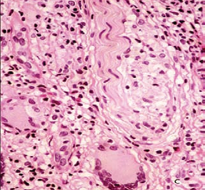

The possibility of TL, BTL, or type 1 leprosy reaction R1, was strongly suspected. PAS, Ziehl-Neelsen (ZN) and Grocott stains didn’t show germs. Small and medium sized vessels were surrounded by giant cells and lymphocytes and elastic fibers stain showed their absence or diminution in the lesion or in the vessels or their phagocytosis by the giant cells (Figure 6).

Figure 6a Medium size vein surrounded by abundant giant cells and lymphocytes.

Figure 6b Elastic stain demonstrates giant cells phagocytosing elastic fibers. A: HE, 20X. B, 40 X.